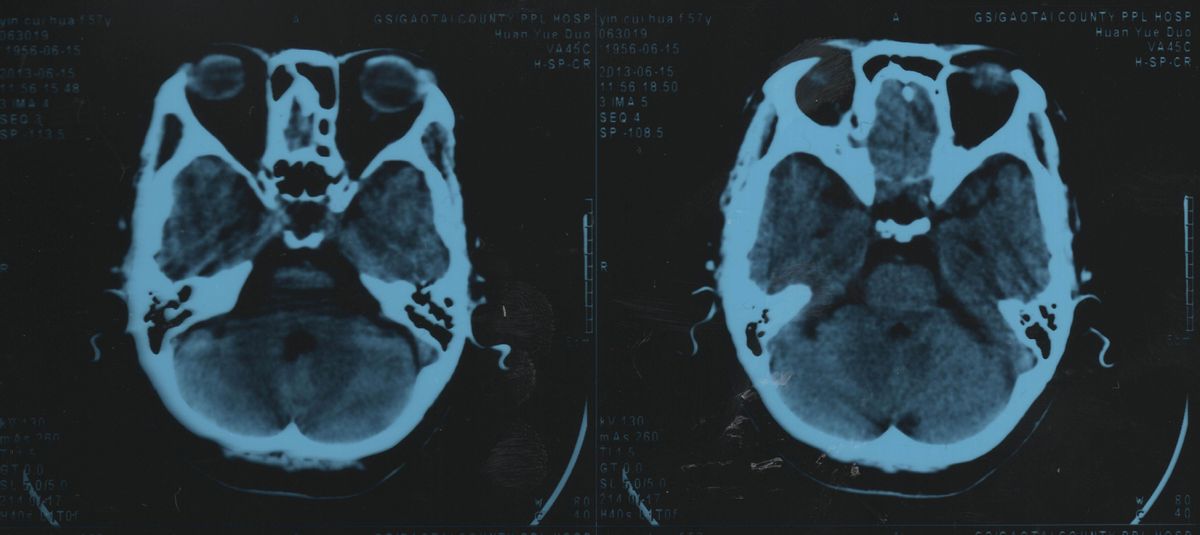

脑脊液:淡淡的甜味

更温和的味道则来自我们大脑的脑脊液 ,这是一种保护和支撑脑子的重要体液,在头骨和软体组织之间,充当了重要的减震减压作用。

脑脊液含有大量葡萄糖,

无色透明,平均浓度450~750mg/L。 除此之外,再没有什么其他多余的杂质,所以对人体来说重中之重的脑脊液,只有一股淡淡的、纯粹的甜味。